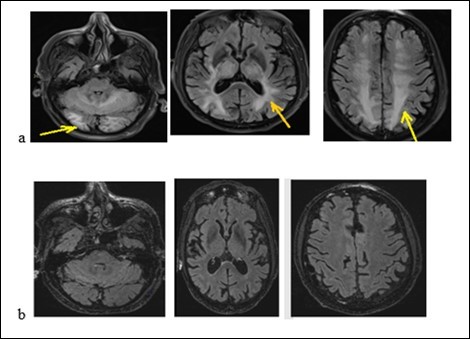

An old man of 74 called J. R. was admitted to hospital on January 26, 2018 for generalized tonic-clonic seizures. The symptoms began 2 weeks before his admission by abdominal pain, vomiting, diarrhea without fever. They were followed by generalized tonic-clonic seizures. According to his medical history, he suffers from high blood pressure, non-insulin-dependent diabetes, chronic obstructive pulmonary disease (COPD), moderate renal failure on a single kidney. He underwent a left nephrectomy for a papillary urothelial tumor, a right upper pulmonary lobectomy for the removal of a bronchial adenocarcinoma. He has been treated with Gemcitabine (Gemzar) and by Fluorine uracil (Folfox) for a pancreatic adenocarcinoma. He also has 3 adrenal nodules. The physical examination noted drowsiness but the patient was reactive to minor stimuli with a Glasgow score of 13/15, a flaccid right hemiplegia. We noted that there was not a neck thifness. Besides, the blood pressure was 210/95 mm Hg and the heart rhythm was regular without heart murmur or additional noises. The rest of the physical examination was normal. The biological check-up had shown a creatinine level at 203 micromol/l with a clearance at 29.9 ml/min, a hyperkalaemia at 6 mmol/l and a hypercalcemia at 2.62 mmol/l. The CSF study had shown a hyperproteinorachy at 0.940g / l, a glycorachy at 5.6 g/l, the CSF count cell displayed 6 cells/mm3 without germ. The brain MRI (Figure 4a) had displayed on flair sequences, diffuse and symmetrical hyper signals of the sub-cortical white matter of the temporal, occipital, frontal lobe and the cerebellum. These radiological findings evoked a RPE syndrome. The treatment included hyperhydration and an anti-epileptic drug. The outcome was noticeable with the decrease of symptoms. We relied on the diagnosis of RPE syndrome. The brain MRI checking-up (Figure 4b) at 40 days was displaying a complete decrease of the lesions.

Figure 4.Brain MRI with flair sequences showing hyper signals of white matter and cerebellum corresponding to edema (a) and the decrease of lesions after treatment (b).